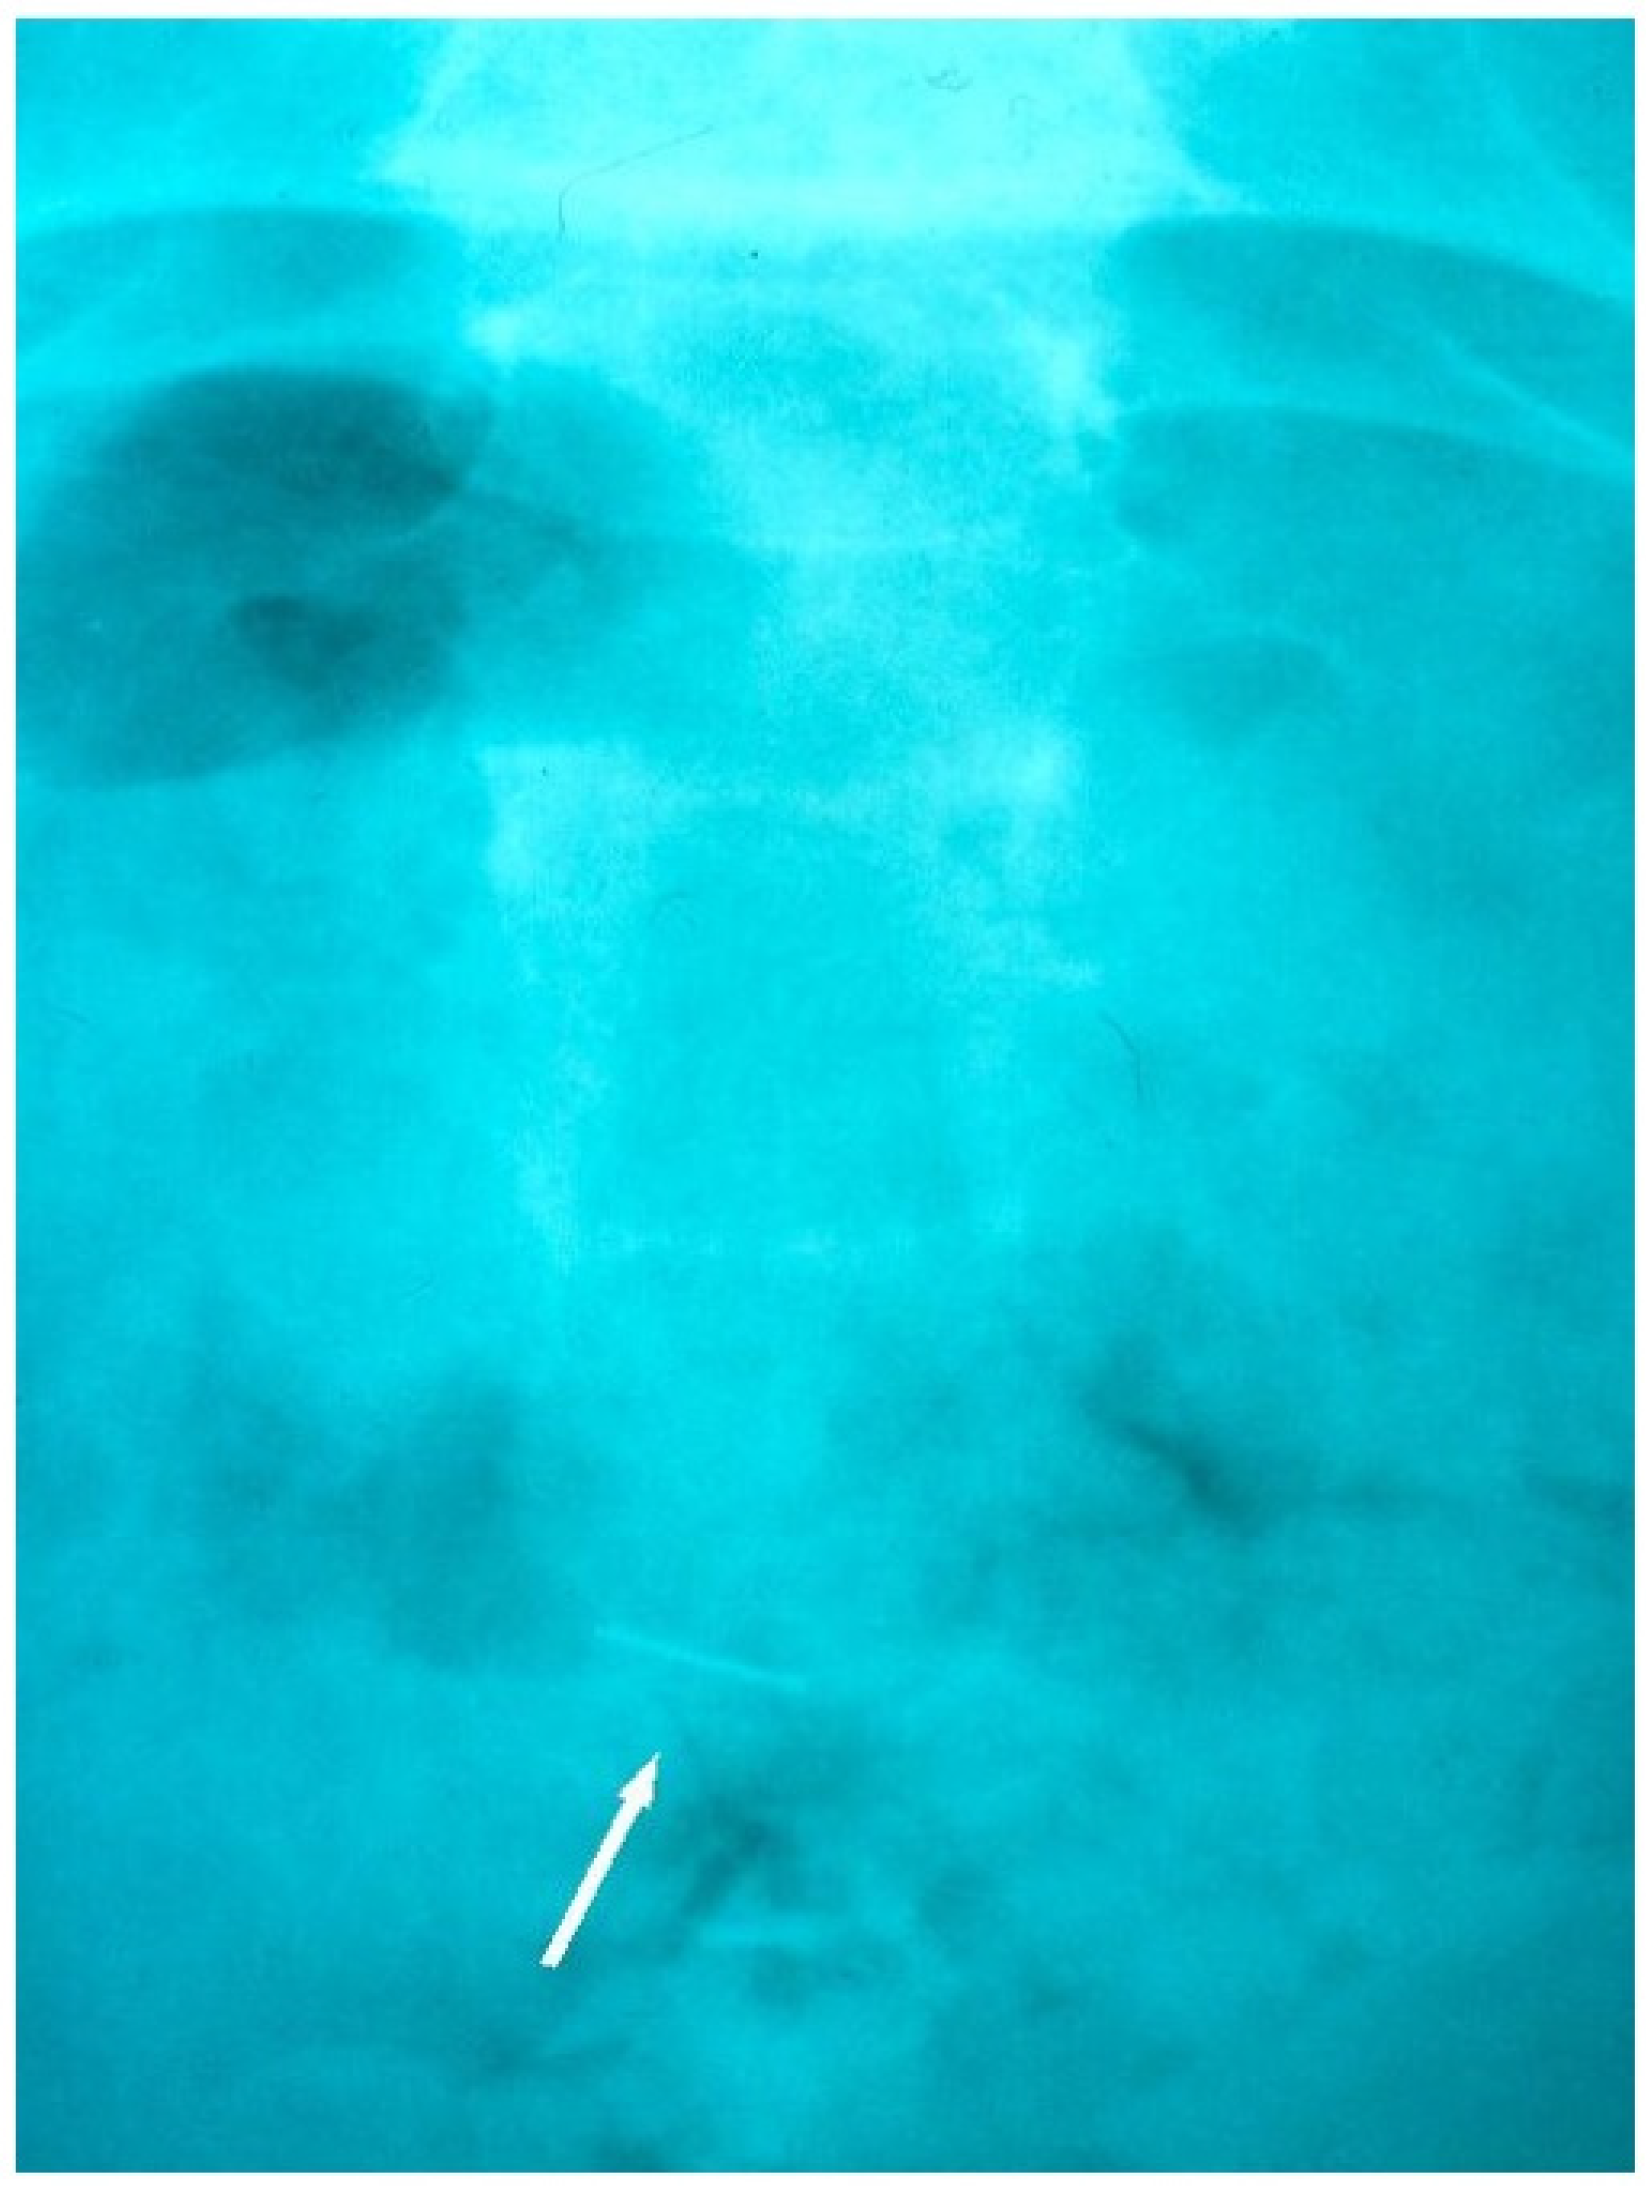

Radiographic tracking view showing the archwire fragment in the rectal area, prior to its natural evacuation from the GIT.